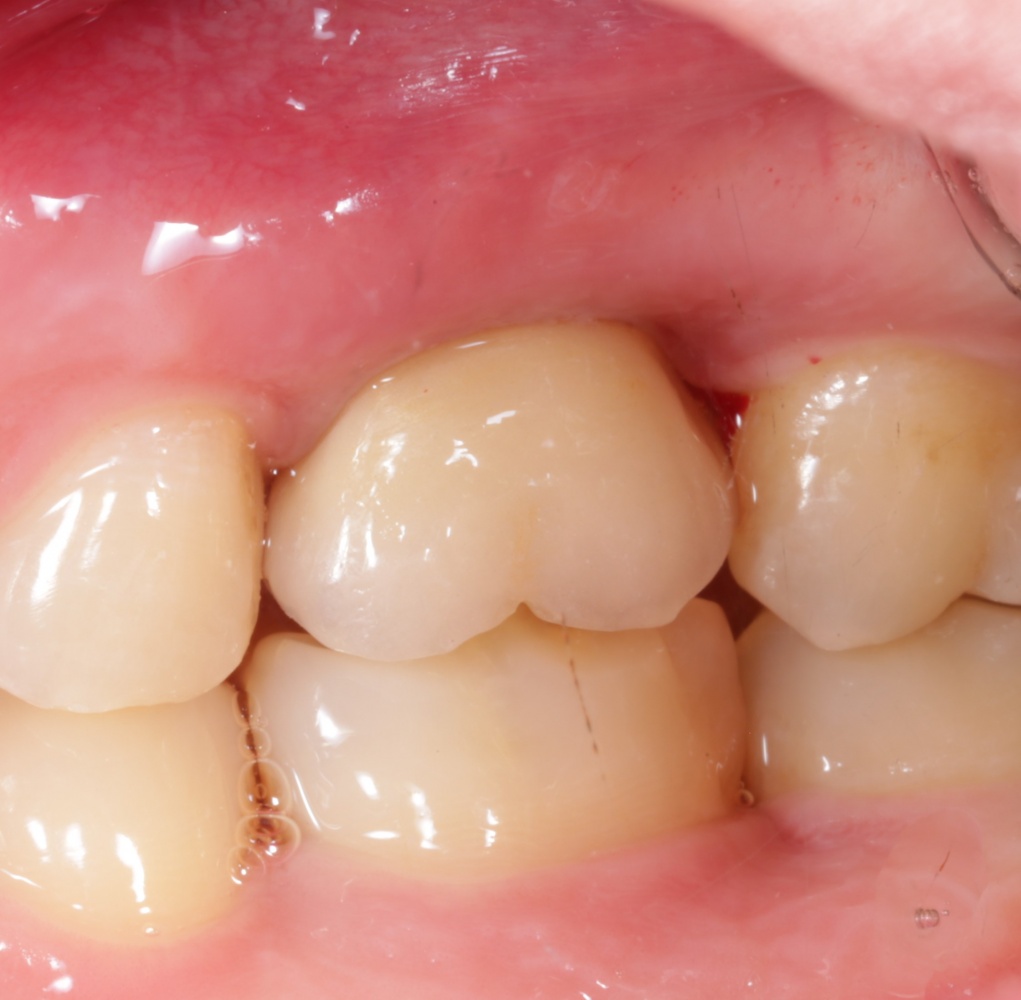

А через два месяца — вот так:

На этом этапе, для создания более правильного десневого контура, можно поменять формирователь размер больше:

А еще через месяц — поставить временную коронку:

Могли бы мы в этом случае обойтись без аугментации лунки? Вполне, могли бы. Но в этом случае окружающие коронку ткани выглядели бы иначе, а сам пациент испытывал бы проблемы с уходом — из-за утраты объемов, у него постоянно застревали бы остатки пищи между коронкой и десной.